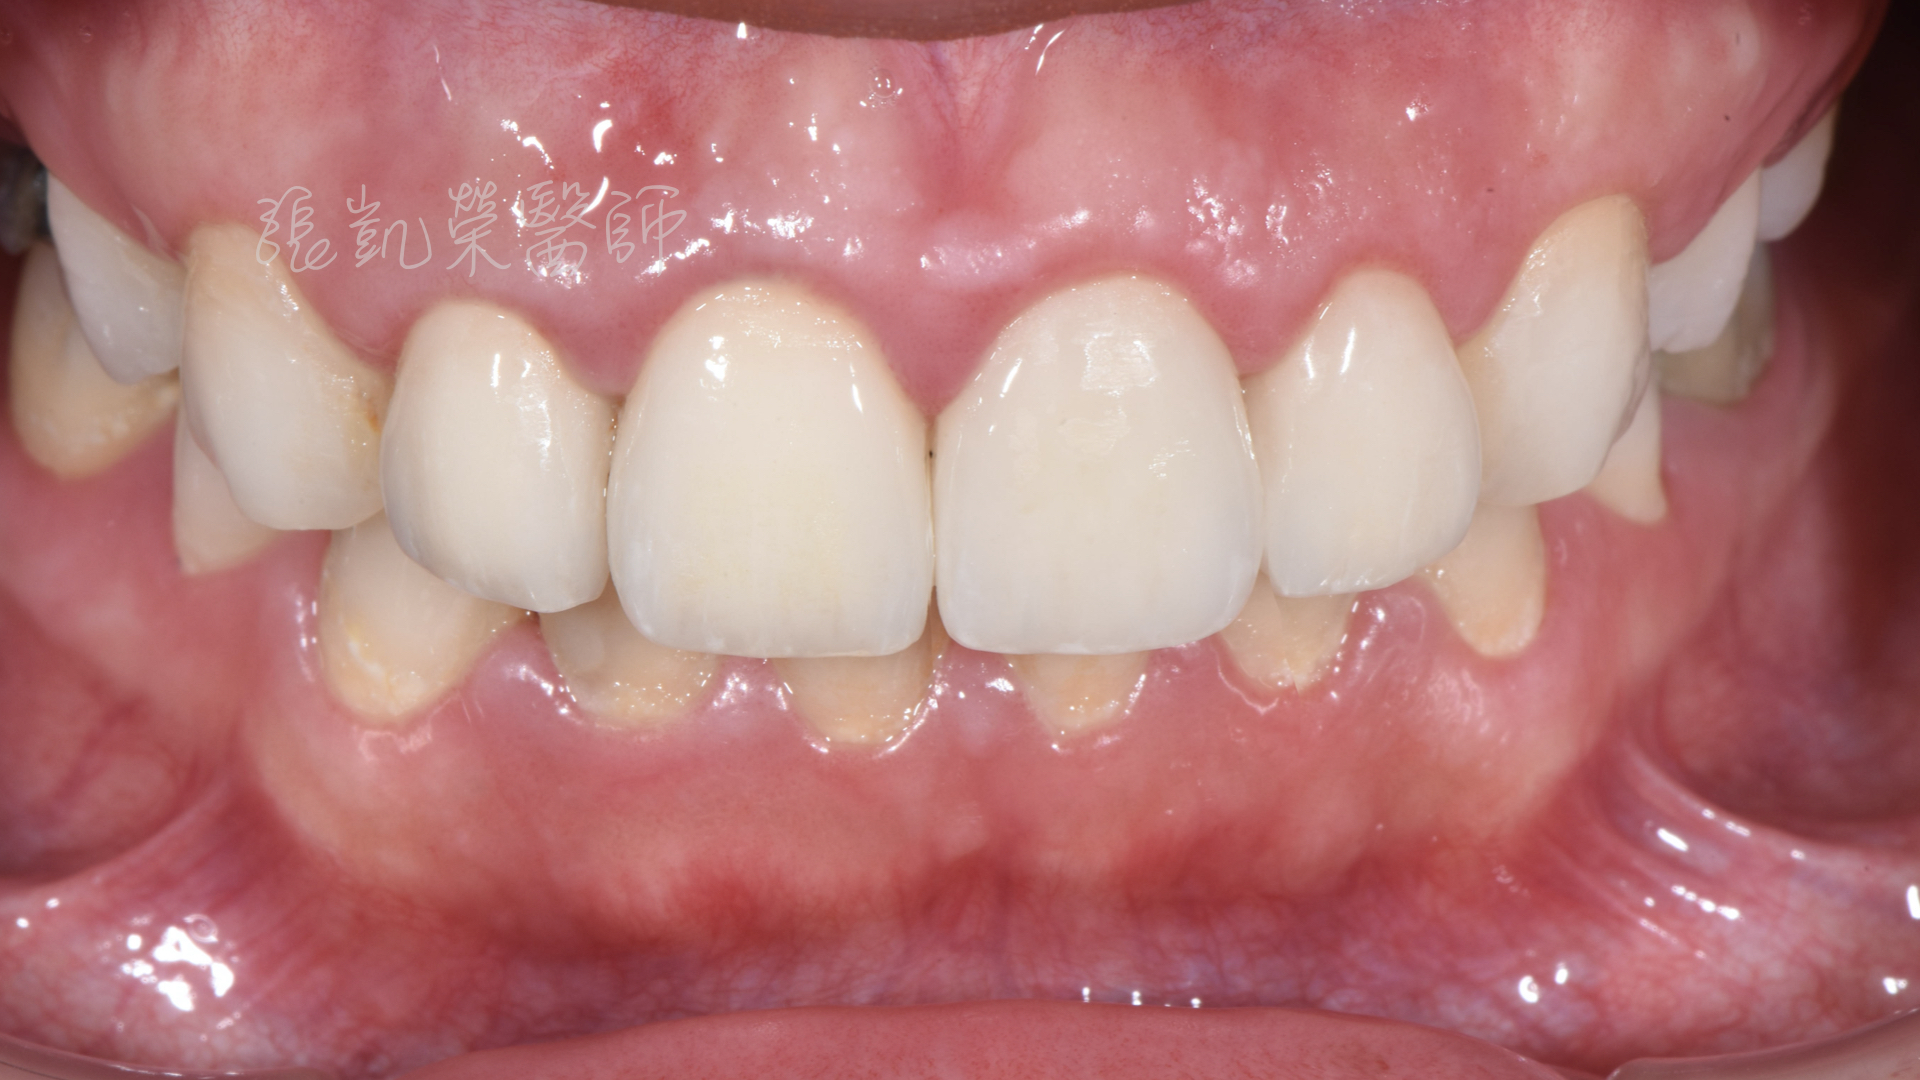

榮醫師檢查後發現,除了牙齒顏色外,還有中線偏斜、水平不齊、門牙大小不均、牙齦高低不齊等問題。

榮醫師建議先做牙齦整形術,將牙齦的位置調整齊,再用美白讓牙齒顏色亮白。

但除了做過根管治療的牙齒,牙齒較脆弱用全瓷冠修復外,其餘兩顆門牙為了減少傷害,用貼片修復,可以改善型態與大小,讓整體顏色、形態、中線水平做一併調整。